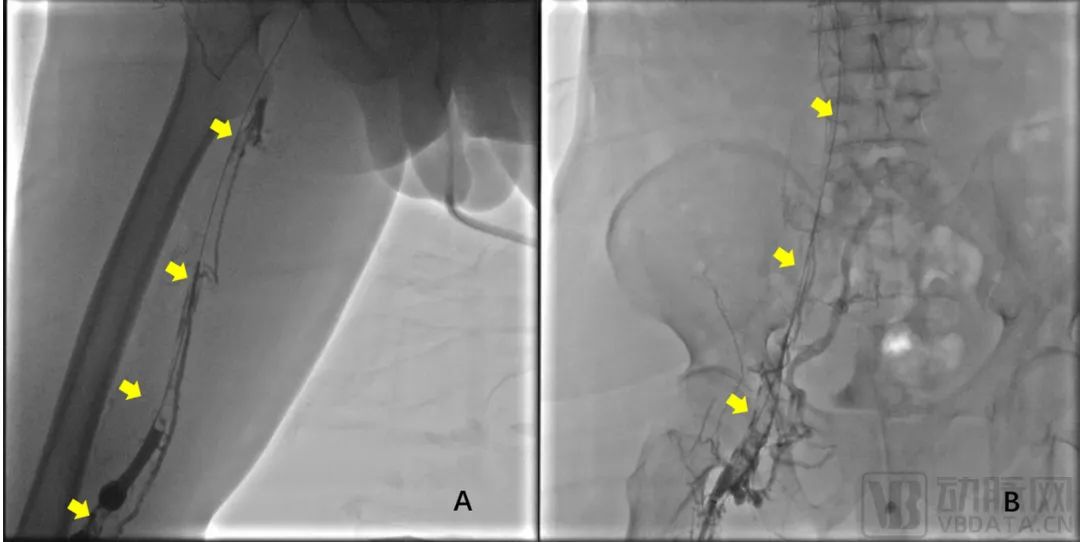

2023年8月16日,赣州市人民医院(南方医院赣州医院)血管外科叶波教授及其团队,应用“荷声”超声辅助溶栓导管为一例下肢深静脉血栓形成的中年男性患者成功进行了微创除栓治疗,成功完成了“荷声”超声辅助溶栓导管首例临床FIM试验,具备重大里程碑意义。患者右下肢肿胀十天余,加重伴小腿水泡形成5天。彩超和静脉造影均显示:下腔静脉下段、右髂股腘静脉全程血栓,管腔完全闭塞(图2)。

图2 A:右腘静脉、股静脉全程血栓(黄箭头)、血流阻塞 B:右股总、髂外、髂总静脉和滤器下方下腔静脉全程血栓(黄箭头)、血流阻塞